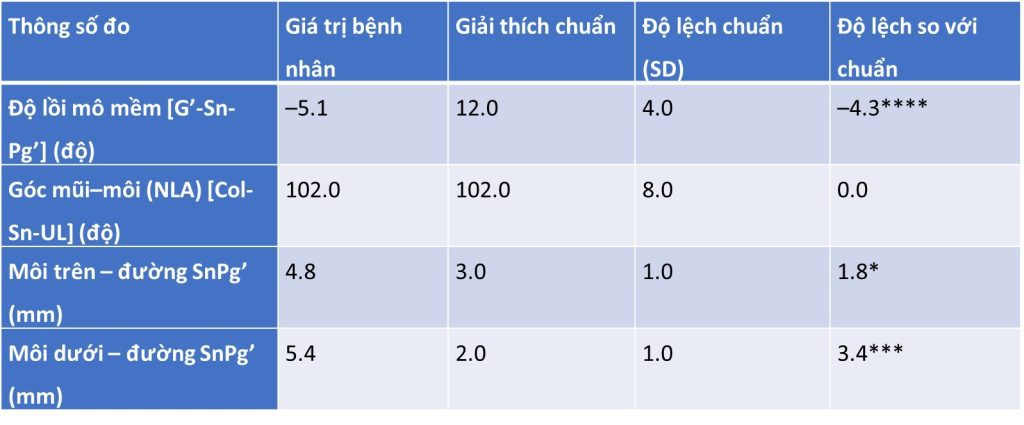

Tóm tắt phim sọ nghiêng (hình 2-16 và bảng 2-11 đến 2-14)

Tương quan xương hạng III với profile xương lõm, bao gồm:

- Xương hàm dưới nhô ra so với nền sọ

- Khớp cắn bù trừ với răng cửa hàm trên nghiêng ra trước và răng cửa hàm dưới nghiêng vào trong

- Chỉ số Wits loại III

- Profile mô mềm lõm

- Môi dưới nhô ra

- IMPA thấp hơn chuẩn 1,2 SD → răng cửa dưới hơi nghiêng vào trong.

- U1–Palatal plane cao hơn chuẩn 1,3 SD → răng cửa trên nghiêng ra trước.

- Góc liên răng cửa cao hơn chuẩn 1,1 SD → khớp cắn bù trừ (răng cửa trên nghiêng ra, răng cửa dưới nghiêng vào).

- Wits âm nhiều (–5,7 mm, lệch 4,7 SD) → đặc trưng của sai khớp cắn hạng III xương.

NLA = Góc mũi–môi (nasolabial angle).

UL = Môi trên (upper lip).